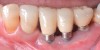

Fig 4. Clinical view of the area 3 months post-therapy. Shallow probings of 3 mm were present around the dental implants with absence of bleeding. However, the mucogingival deformities remained on the premolar implants and would require treatment.

Figure 4

Dental implants have revolutionized the way in which clinicians treat and restore partially and fully edentulous patients and have demonstrated success for managing a broad range of clinical dilemmas. While implants have been highly predictable and have achieved long-term success, they are not immune from complications associated with improper treatment planning, poor surgical and prosthetic execution, material failure, and inadequate or infrequent maintenance. Among these problems are the biologic complications of peri-implant mucositis and peri-implantitis, which are inflammatory conditions in the soft and/or hard tissues surrounding dental implants (Figure 1 through Figure 4).1,2